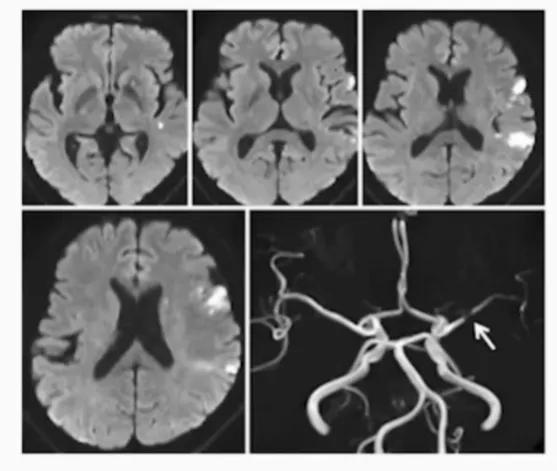

★ 双侧前后循环多发斑点状